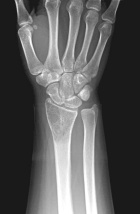

18 year old female with persistent and worsening wrist pain for four months